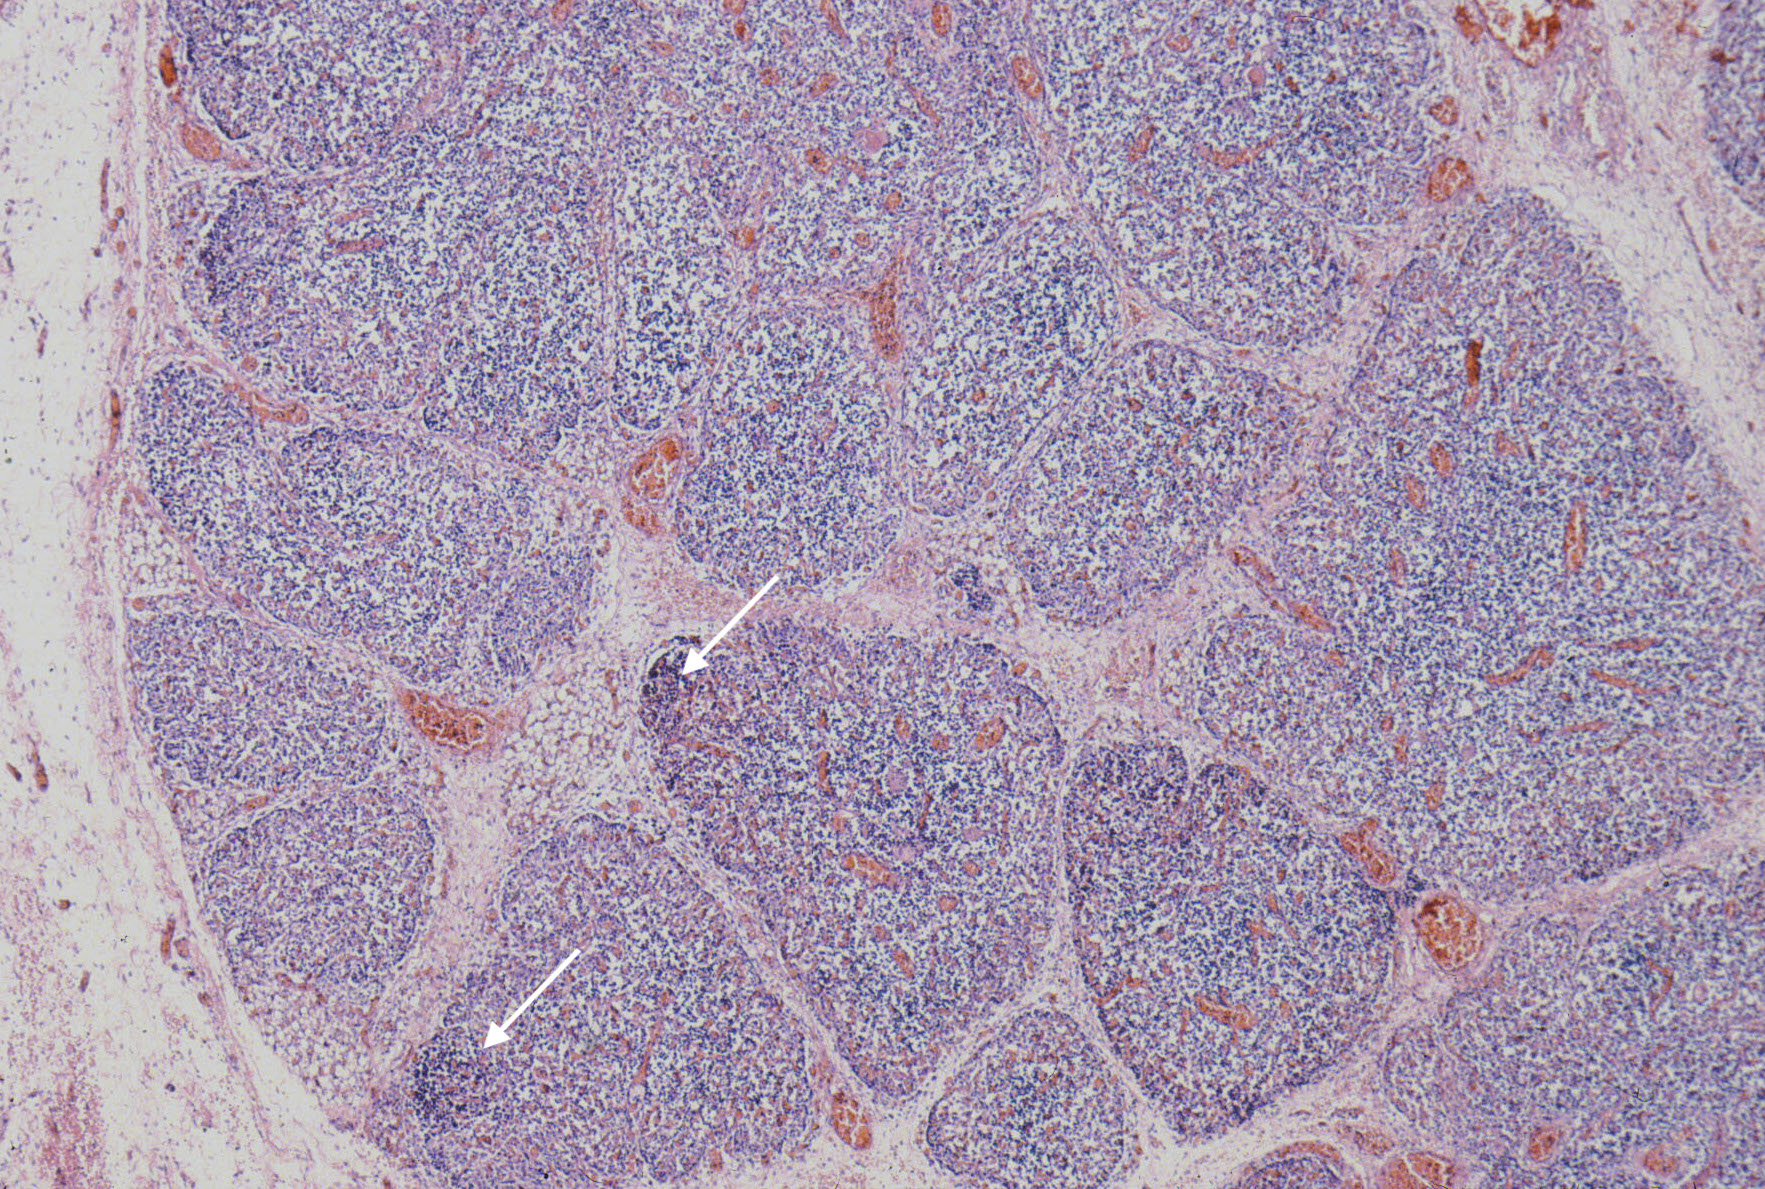

The thymus normally involutes as the infant ages. However, in some stillborn infants, usually with a chronic stress such as infection, fetal hydrops or growth restriction, there is accelerated involution, that is loss of the lymphocytes in the cortex of the thymus. An early phase of this process is often seen in response to chorioamnionitis. In the acute cases, the prominent abnormality is a “starry sky” appearance due to the lymphorrhagia (phagocytosis) of cortical lymphocytes. Low magnification microscopy demonstrates open spaces in the cortex reminding some observers of a “starry sky”. (Fig 9,10) At higher magnification, these apparent spaces can be seen to be the cytoplasm of a large cell often with small, fading nuclei of small lymphocytes within.

As involution progresses, there will be a progressive loss of cortical lymphocytes. The cortex will appear notably thinned compared to the medulla with thinner lobules and more connective tissue between lobules (Figs 11a, 11b, 12a, 12b, 13a, 13b).

At the extreme, the medulla will appear to have the only small lymphocytes in the thymus, giving an inside out appearance at low magnification (fig 14, 15).

A staging system has been proposed for this progression: stage 0 = no histopathologic changes, stage 2 = starry sky appearance, stage 3 = loss of distinction of the medulla and cortex, and stage 4 = loss of all cortical lymphocytes with an inverted appearance[16]. Based on the clinical histories, the stage has been correlated with duration of involution as follows: stage 0 = 0-12 hours, stage 1 = 12-24 hours, stage 2 24-48 hours, and stage 4 > 72 hours. A continuous stress keeps the thymus involuted, and results in decreased weight as demonstrated in human autopsy and in experimentally in the monkey with repetitive dexamethasone injections [17].The thymic to brain weight usually reflects the histological degree of involution when the small size is due to histological identified involution and not a failure of thymic development.